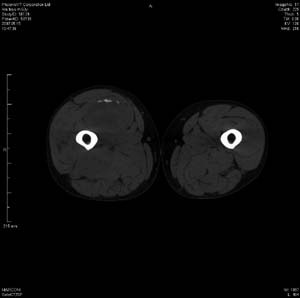

男 63岁 右大腿无痛性肿块11年,x片右大腿软组织肿块影,余无明显异常.ct值-13__239hu

右大腿股内侧股与收肌间隙间多发囊实性占位,界清.内示斑点状钙化.局部骨质无异常.肌肉推压移位表现.

考虑肌间隙病变.可有1,神经来源肿瘤.2,血管来源病变.3,淋巴来源肿瘤.4,脂肪来源肿瘤.5,滑膜来源肿瘤.结合病史只能考虑良性占位.建议增强或mri进一步分析.

同意,病史较长,病变周围分界清晰,考虑良性病变。病灶内有多发斑点状钙化,沿肌间隙生长,血管瘤或淋巴管瘤首先考虑。